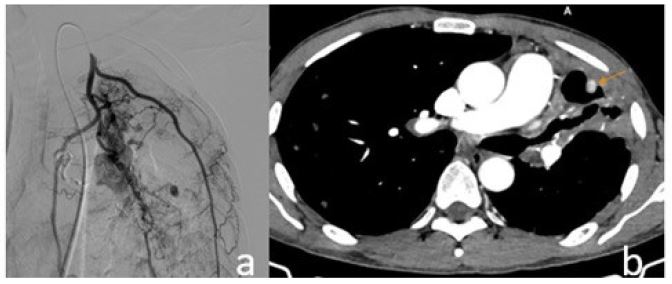

The patient initially underwent endovascular embolization. Selective angiography of the left internal mammary artery identified the pseudoaneurysm, which was embolized using NBCA glue mixed with lipiodol at a 1:4 ratio. Despite this, the patient continued to experience mild, intermittent hemoptysis. Follow-up CT imaging showed complete occlusion of the left bronchial artery and collateral branches from the left subclavian artery, but the pseudoaneurysm persisted with reduced contrast enhancement.

Figure 2: (A) Pseudoaneurysm visualized on selective angiography of the left internal mammary artery, followed by selective embolization using glue. (B) Post-procedural image after the first intervention shows the pseudoaneurysm with reduced contrast enhancement compared to baseline.

In this clinical case, the pseudoaneurysm was associated with a residual tuberculous cavity and supplied by both bronchial and non-bronchial systemic arteries—features typical of tuberculous-related intrapulmonary pseudoaneurysms. The initial management involved embolization of systemic branches via the left internal mammary artery with NBCA glue, which resulted in a partial, but not complete, occlusion. The pseudoaneurysm persisted, although with reduced contrast enhancement. This scenario highlights the limitations of isolated systemic embolization in complex cases, especially when target vessels are small and difficult to access.